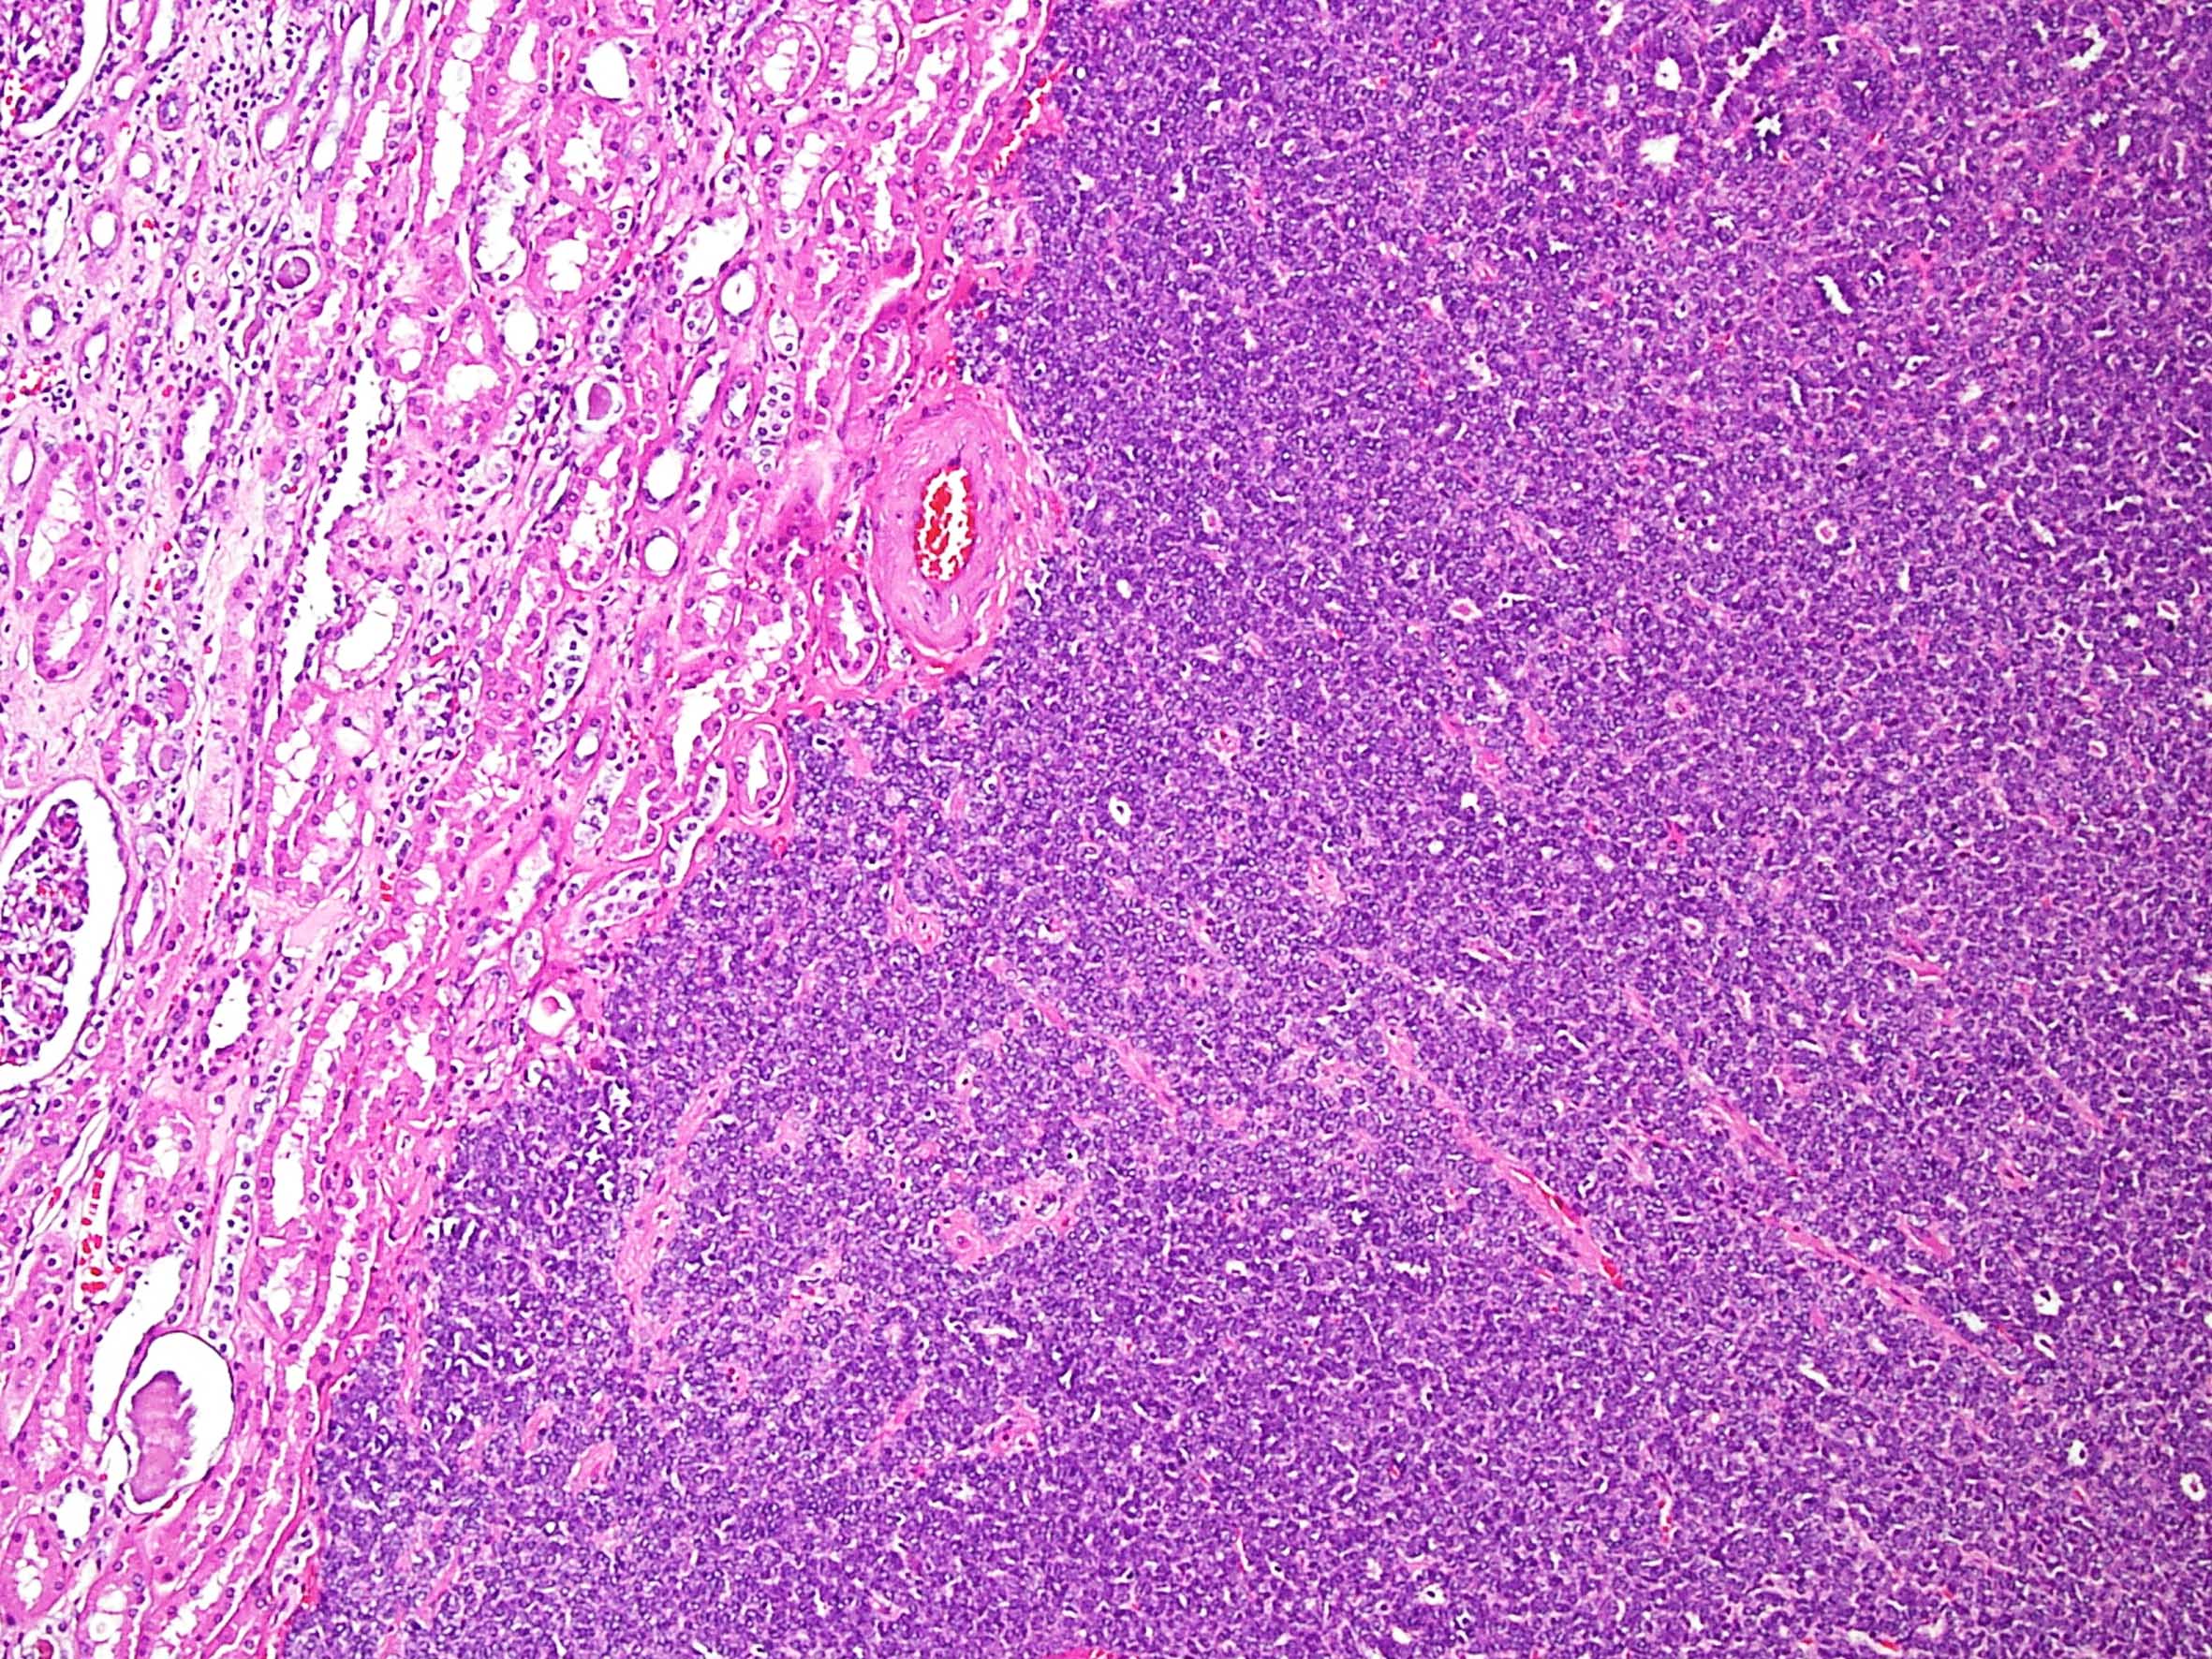

Case description (by case creator):

Metanephric adenoma